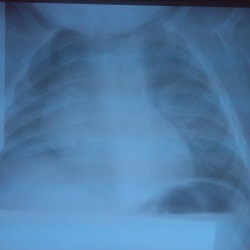

Принесли снимок из поликлиники. Направление без диагноза. Думаю описать как тимомегалию или же это из за того, что снимок сделан с поворотом?